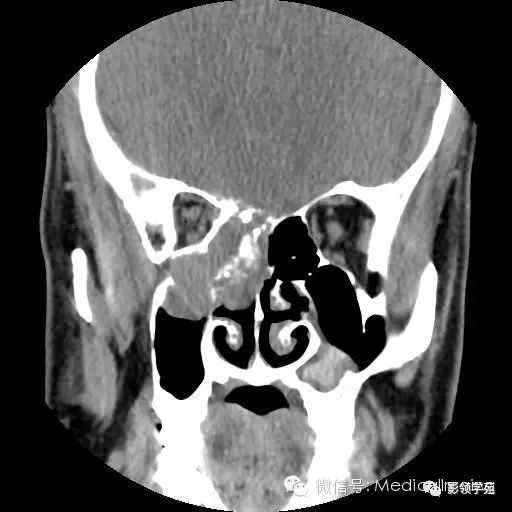

鼻窦恶性肿瘤

鼻腔及鼻窦恶性肿瘤